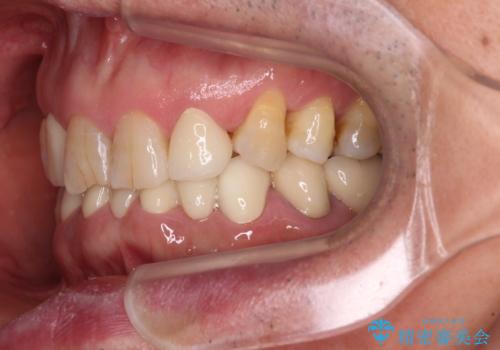

- 乳歯や矮小歯が多くある前歯部の審美障害が気にして来院された患者様です。

上顎の矮小歯は隙間が多く、歯軸の傾斜も大きかったため、部分矯正により補綴治療前に歯の位置を整えることとしました。

前歯部はディープバイトという、上顎前歯が下顎前歯に深く覆い被さる咬合であったので、理想的には全顎矯正が必要となりますが、今回は患者希望により前歯部のみの部分矯正で対応しました。そのため下顎犬歯の神経を取り除くことになってしまったのは心残りであります。